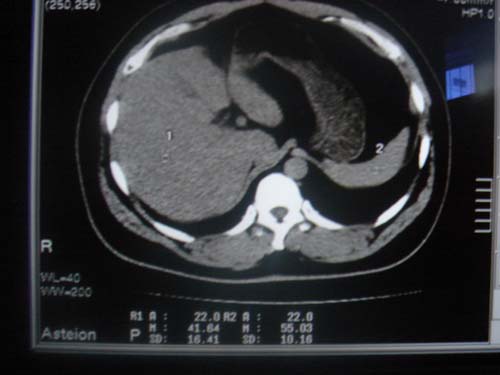

患者 男 40 右上腹不适 有胆囊息肉病史2年

最后二副图像示胆囊壁增厚,与肝分界欠清,建议强化ct或磁共振

片中示肝脏的ct值低于脾脏,肝脏右叶外缘部份凹凸不平,考虑脂肪肝,肝硬化可能。结合其检查如b超或ct增强检查。

胆囊未见明显异常,肝脏密度似比脾脏密度低,测量一下ct值排除一下脂肪肝.当然做一下增强或mr就更好了.

肝右叶密度不均,脾大。强烈要求增强扫描除外浸润型肝癌。

肝大   密度降低  脾大  脂肪肝?